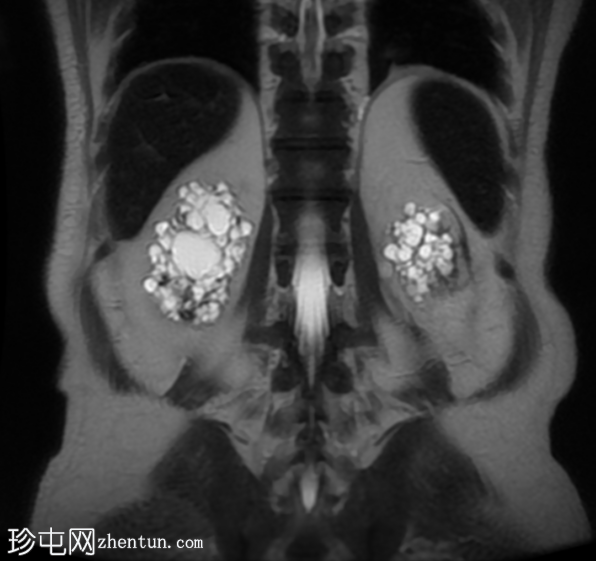

MRI

冠状位

T2加权像

双侧肾囊性疾病,可见多个肾囊肿,其中许多呈复杂性(出血性)囊肿,T1加权像呈高信号,T2加权像呈低信号。

左侧可见一较大的肾周血肿,与上极出血性囊肿相连,提示出血性囊肿破裂(Wunderlich综合征)。

未见肾脏软组织肿块。

轻度肝脾肿大,受检骨骼T2加权像呈弥漫性低信号,提示肾性骨营养不良。